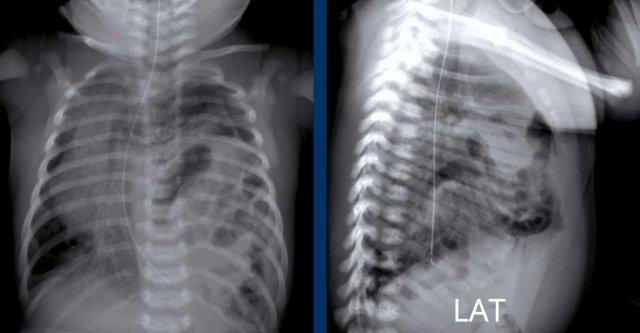

Những hình ảnh này là của một trẻ sơ sinh đủ tháng với

khó thở.

Hình ảnh

Mờ một phần vùng nửa ngực trên bên trái.

Các quai ruột được nhìn thấy trong nửa lồng ngực bên trái.

Sự dịch chuyển của các cấu trúc đường giữa được thể hiện qua sự lệch của ống thông dạ dày qua mũi

(đầu mũi tên).

Phim ngực tư thế nghiêng cũng cho thấy các quai ruột trong lồng ngực.